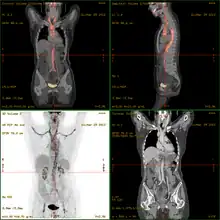

- 18F-fluorodeoxyglucose positron emission tomography/computed tomography (FDG-PET/CT)has become a widely used imaging tool in patients with suspected Large Vessel Vasculitis, due to the enhanced glucose metabolism of inflamed vessel walls.[13] The combined evaluation of the intensity and the extension of FDG vessel uptake at diagnosis can predict the clinical course of the disease, separating patients with favourable or complicated progress.[14]